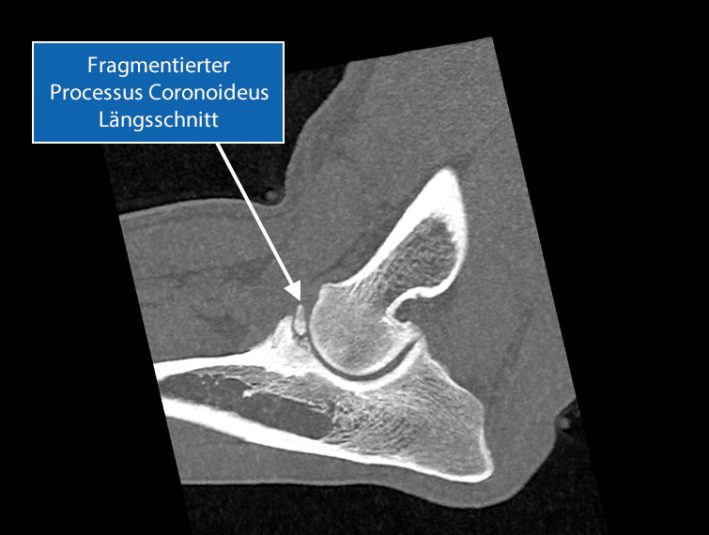

Fragmentierung des Processus Coronoideus

Eine Fragmentierung des Processus Coronoideus stellt eines der häufigsten Probleme im Zusammenhang mit einer Ellbogendysplasie dar.

SLT Laengsschnitt Ellbogen ED FCP

Das abgebrochene Fragment (FCP) kann im weiteren Verlauf den Gelenksknorpel am Humerus condylus beschädigen, sodass der Knochen nicht mehr von einem Knorpel überzogen ist.